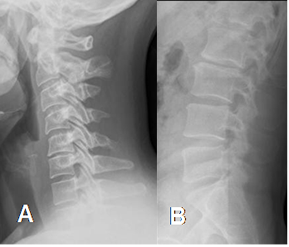

El dolor se aumenta con la flexión y las maniobras de valsalva. La columna se rectifica y pierde movilidad por espasmo muscular. (21). (Fig 81).

Fig 81. Espasmo muscular.

A: Rx lateral cervical y B: Rx lateral lumbar. Pérdida de la lordosis cervical y lumbar, por espasmo muscular.